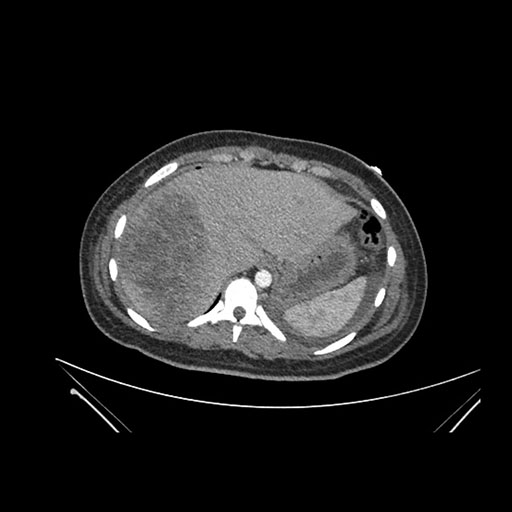

Imaging Analysis

Look through the patient's CT scan to identify any areas of concern for the necessary procedure.

Coronal Arterial

Based on initial findings, which issue(s) would you be most concerned about?